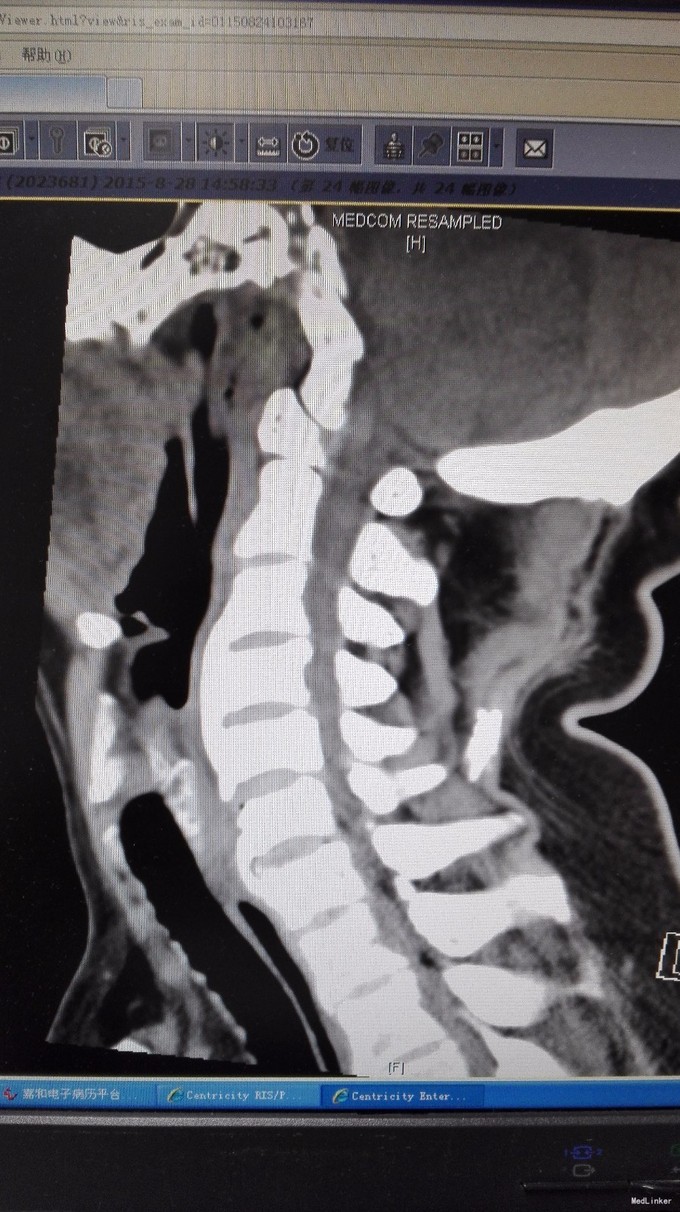

查体:双手麻木感,肱三头肌肌腱反射活跃,左侧髂腰肌4级,臂丛牵拉实验阴性,椎间孔挤压实验阴性。 辅查:CT:C2-7椎间盘突出,继发性椎管狭窄,OPLL,OFL。

诊断:混合型颈椎病(脊髓型+神经根型) 治疗:颈后路3-7单开门椎管扩大成型术(锚定法)